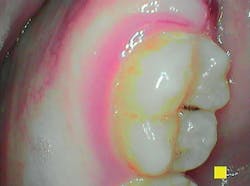

Perio mode allows the clinician to provide a more complete assessment of the patient’s oral health by rapidly assessing gingival inflammation, plaque, and calculus.2 Through the usage of LED lights, the camera demonstrates new plaque, which is shown as white, and the old plaque that is demonstrated in a yellow and orange shade.2

This allows patients to see the bacteria that was left behind even after their most recent brushing, which increases their need to change their oral health regime. The degree of gingival inflammation is detected with a light pink color to represent mild inflammation through a deep magenta to represent severe inflammation.2